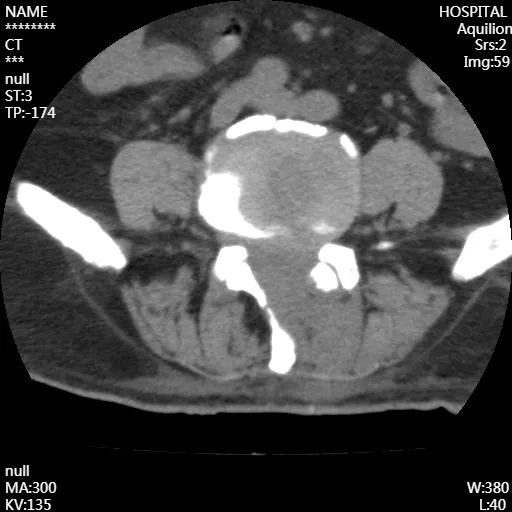

术后

腰椎CT成像

从影像上看出,患者术后神经压迫情况得到了改善